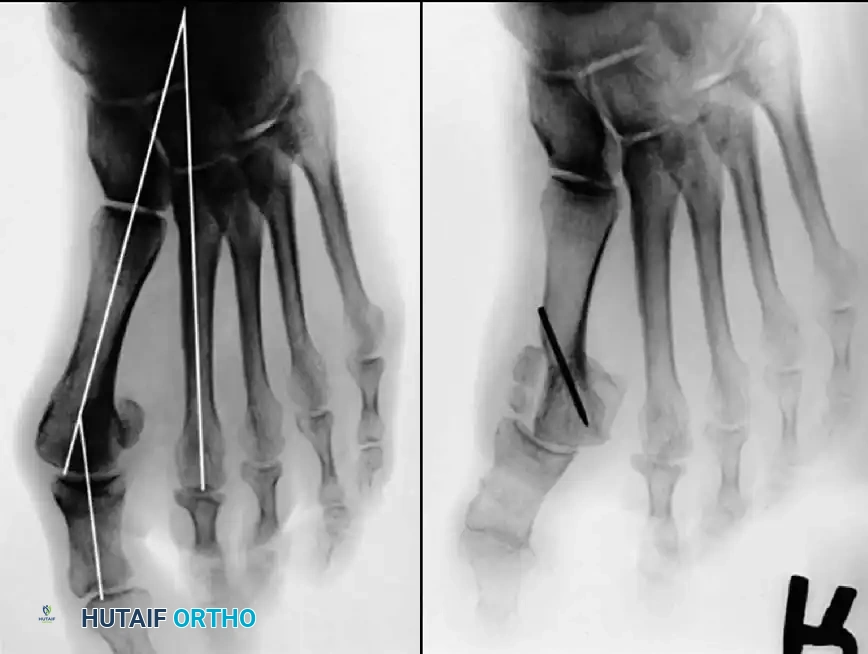

Inadequate vascularity or sensibility should be investigated thoroughly before bunion surgery is considered. In addition, the position of the articular surface of the metatarsal head in relation to the longitudinal axis of the fi rst metatarsal should be determined (Fig. 78-8). Standard preoperative radiographs should include standing dorsoplantar and lateral views, a nonstanding lateral oblique view, and axial sesamoid views (Fig. 78-9). The hallux valgus angle and the fi rst-second intermetatarsal angle should fi rst be drawn on the standing dorsoplantar view by bisecting the shafts of the bones (Fig. 78-10), with an awareness of the normal ranges. These angles are most frequently cited as guidelines for treatment decisions, but Donnelly et al. reported that interobserver measurements of the hallux valgus angle varied by approximately 6 degrees and of the intermetatarsal angle by 4 degrees. They cautioned that potential errors in measurement should be considered when these parameters are used to make treatment decisions. The hallux valgus interphalangeus angle and any evidence of degenerative arthritic changes at the fi rst metatarsophalangeal or metatarsocuneiform joints should be documented. Oddities may be present and, if overlooked, may compromise a technically well-done procedure. Mann emphasized that the presence of an os inter-

A B

Fig. 78-8 A, Determination of position of articular surface of metatarsal head in relation to longitudinal axis of fi rst metatarsal. B, Measurement of distal metatarsal articular angle at time of surgery. Markings are at medial and lateral margins of articular surface of fi rst metatarsal head and longitudinal axis of fi rst metatarsal shaft. metatarseum between the bases of the fi rst and second metatarsals might preclude the effectiveness of a soft-tissue procedure alone to provide suffi cient correction of the increased intermetatarsal angle. Likewise, accessory sesamoids and prominent ungual tuberosities at the interphalangeal joint contribute to a painful callus at the tibial side of this joint. An os tibialis externum frequently is associated with excessive hallux valgus interphalangeus. Varus of the fi rst metatarsal might be a signifi cant part of the overall deformity of the foot even with an intermetatarsal angle of less than 10 degrees. Metatarsus varus with a relatively small hallux valgus angle (15 to 20 degrees) may produce signifi cant deformity even though the angles are not excessive. The usefulness of computer-assisted compared with manual measurement of the intermetatarsal angle, hallux valgus angle, and distal metatarsal articular angle is still uncertain. Both methods have closer interobserver and intraobserver correlation in measurement of the intermetatarsal angle and hallux valgus angle than in measurement of the distal metatarsal articular angle. The reliability of either method has such a wide range (5 degrees), however, that measurements of these angles, although useful as a guide, do not provide a completely reliable indication of the magnitude of deformity. Condon et al. suggested that the reliability of the intermetatarsal angle can be improved by careful technique and by making the measurements at least twice and averaging them. Schneider et al. reported two methods of determining angular measurements based on distinctly different reference points: (1) a longitudinal axis of the fi rst metatarsal using middiaphyseal reference points, and (2) a center-head technique using a center head (center of the articular surface) and center base

(center of the proximal diaphysis) as reference points. They found that measured correction of the hallux valgus and intermetatarsal angles varied by approximately 9 degrees depending on which reference points were used. Recommendations of Coughlin, Saltzman, and Nunley (American Orthopaedic Foot and Ankle Society Ad Hoc Committee on Angular Measurements) included standardized radiographic technique, specifi c placement of reference points (Fig. 78-11), use of a protractor rather than a goniometer for measurements, and, after distal osteotomies, dual measurements using a center-head technique and a Mose sphere.

Fig. 78-10 Method of measuring hallux valgus angle and intermetatarsal angle. Center points are connected, and intersecting lines defi ne angles.